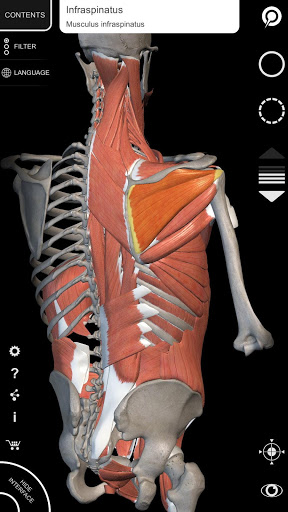

• Hình dung các cơ qua các lớp từ lớp nông đến lớp sâu nhất

• Bằng cách chọn một mô hình hoặc một ghim, thuật ngữ giải phẫu liên quan sẽ hiển thị

• Mô tả các cơ: nguồn gốc, chèn, chi phối thần kinh và hành động